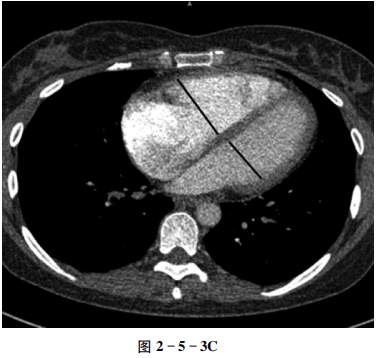

左下肺动脉分支管壁增厚,可见附壁血栓,管腔狭窄,远段肺动脉纤细、僵直(图2-5-3A、B);肺动脉主干增粗;横断位右心室内径与左心室内径之比大于1(图2-5-3C)。